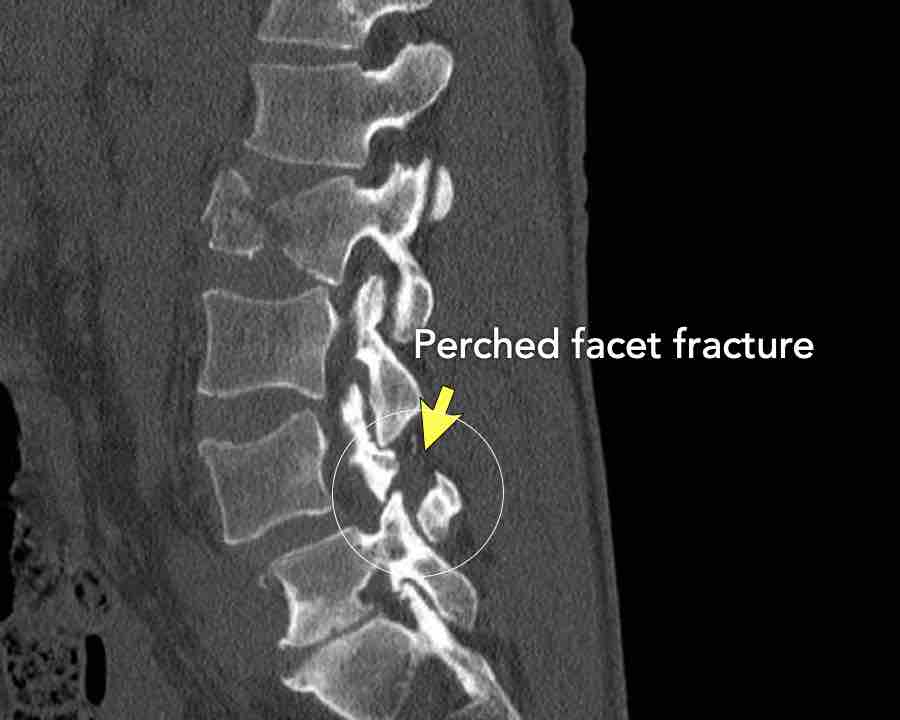

Findings

- Dislocation of the proximal vertebrae anteriorly (white arrow).

- Both facet joints are perched (black arrows). Perched means to be situated above or on the edge of something. In this case the inferior process of vertebral articular joints appears to sit on the ipsilateral superior articular process of the vertebra below.

- Due to the anterior displacement a fracture of the spinous process is seen, in a horizontal oblique course.

Conclusion

Type C injury.